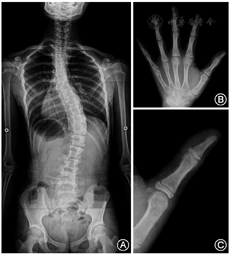

典型病例资料见图1。

TOCI评分依据为内收肌籽骨及拇指各指节的骨骺形态变化[6],其定义为:TOCI 1,内收肌籽骨缺如,拇指远端指骨骨骺未骨化,拇指近端指骨骨骺和干骺端等长;TOCI 2,内收肌籽骨缺如,拇指远端指骨骨骺未骨化,拇指近端指骨骨骺长于干骺端;TOCI 3,内收肌籽骨可见,拇指远端指骨骨骺未骨化,拇指近端指骨骨骺未弯曲成帽;TOCI 4,内收肌籽骨明显,拇指远端指骨骨骺未骨化,拇指近端指骨骨骺开始弯曲成帽但未超过干骺端下端的切线;TOCI 5,内收肌籽骨明显,拇指远端指骨骨骺未骨化,拇指近端指骨骨骺成帽且超过干骺端下端的切线;TOCI 6,内收肌籽骨明显,拇指远端指骨骨骺骨化,拇指近端指骨骨骺未骨化;TOCI 7,内收肌籽骨明显,拇指远端指骨骨骺骨化,拇指近端指骨骨骺开始骨化;TOCI 8,内收肌籽骨明显,拇指远端指骨骨骺骨化,拇指近端指骨骨骺完全骨化。

随访处于TOCI 5的HV为(7.1±2.1)cm/年,处于TOCI 3、4、6和7的HV分别为(4.1±3.0)、(5.8±2.7)、(5.6±2.9)及(2.9±1.7)cm/年,均显著低于处于TOCI 5的HV(均P<0.01)。

身高纵向生长速率峰值(PHV)因测量可靠简便且可直观反映患儿的生长潜能临床应用较为普遍。Hung等[6]发现70.1%的女性AIS患儿于TOCI 5时达到PHV,这表明处以TOCI 5的患儿具有较高的生长潜能和侧凸进展风险。本研究对比分析处于不同TOCI评分的HV,发现处于TOCI 5的HV显著高于其他阶段,进一步证明TOCI 5预示较高的身高生长速率和生长潜能。